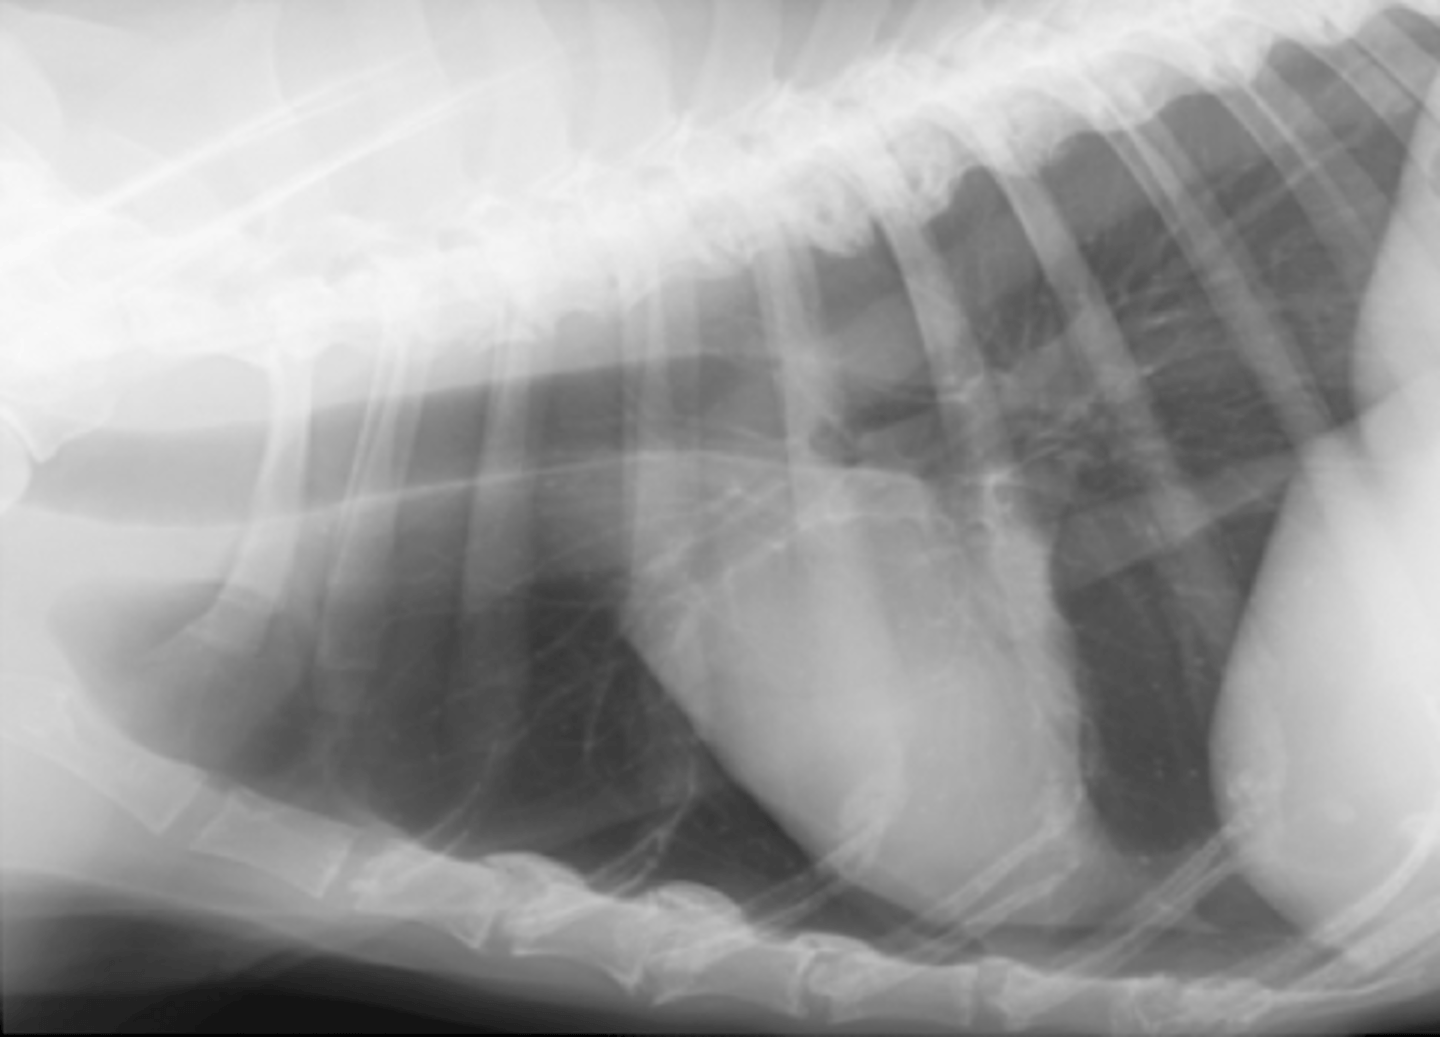

dilatación-torsión gástrica

patología:

microcardias

(silueta separado de la diafragma)

(silueta separado del esternón)